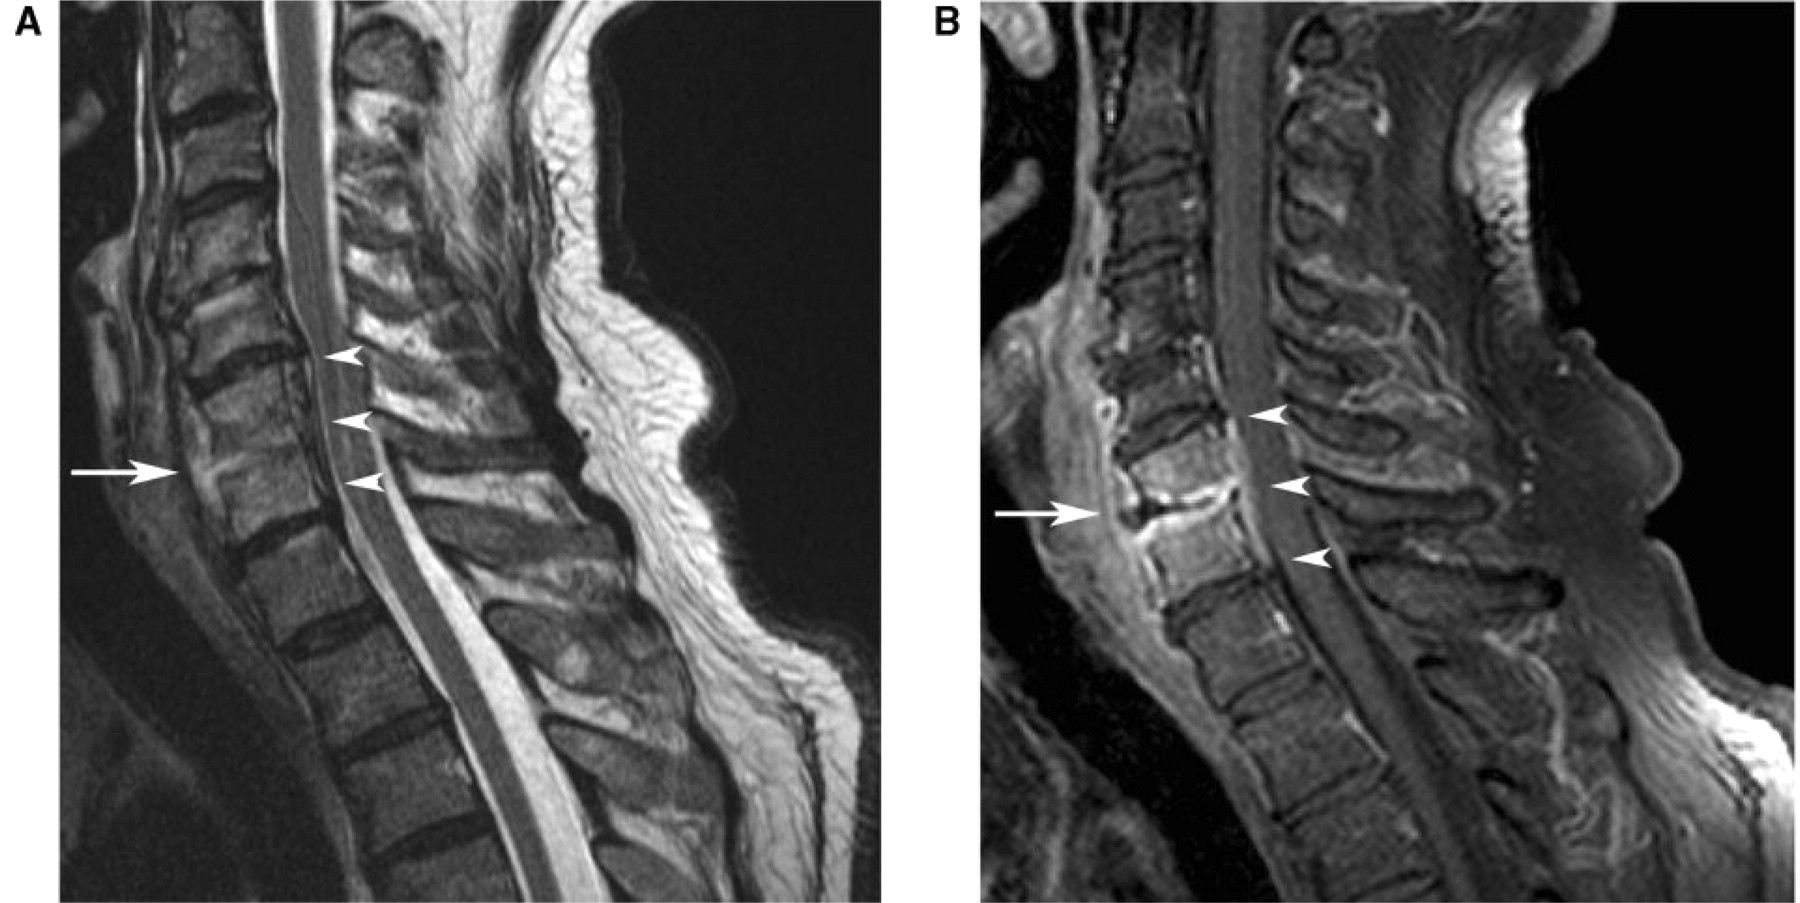

Emergency Medicine EducationSpinal Epidural Abscess Back Abscess Surgery Abscess drainage is the treatment typically used to clear a skin abscess of pus and start the healing process. Smaller abscesses may not need to be drained to disappear. If your abscess does need treatment, we do it right in our office at south florida surgical group. Spinal epidural abscess is a spinal infection caused by a collection of pus. Back Abscess Surgery.

Cureus Epidural Abscess A Cause of Back Pain That Must Not Be Missed Back Abscess Surgery Most abscesses can be managed with a small procedure called an incision and drainage. A laminectomy is a surgical. Simple abscess, such as infected sebaceous cyst on the back, can be drained under local anaesthetic (la) with supplement oral analgesia. Smaller abscesses may not need to be drained to disappear. Procedure the aim of the. Spinal epidural abscess is a. Back Abscess Surgery.

Epidural abscess causes, symptoms, diagnosis, treatment & prognosis Back Abscess Surgery Surgery is often the recommended treatment for spinal epidural abscess. Some small abscesses can be treated with a course. Spinal epidural abscess is a spinal infection caused by a collection of pus or inflammatory granulation tissue between the dura mater and. Smaller abscesses may not need to be drained to disappear. Most abscesses can be managed with a small procedure. Back Abscess Surgery.

Lumbar Epidural Abscess — Institute of Neuro Innovation Back Abscess Surgery Simple abscess, such as infected sebaceous cyst on the back, can be drained under local anaesthetic (la) with supplement oral analgesia. Most abscesses can be managed with a small procedure called an incision and drainage. Surgery is often the recommended treatment for spinal epidural abscess. Smaller abscesses may not need to be drained to disappear. A laminectomy is a surgical.. Back Abscess Surgery.

Epidural Abscess Stepwards Back Abscess Surgery Spinal epidural abscess is a spinal infection caused by a collection of pus or inflammatory granulation tissue between the dura mater and. Procedure the aim of the. Most abscesses can be managed with a small procedure called an incision and drainage. Surgery is often the recommended treatment for spinal epidural abscess. A laminectomy is a surgical. Abscess drainage is the. Back Abscess Surgery.